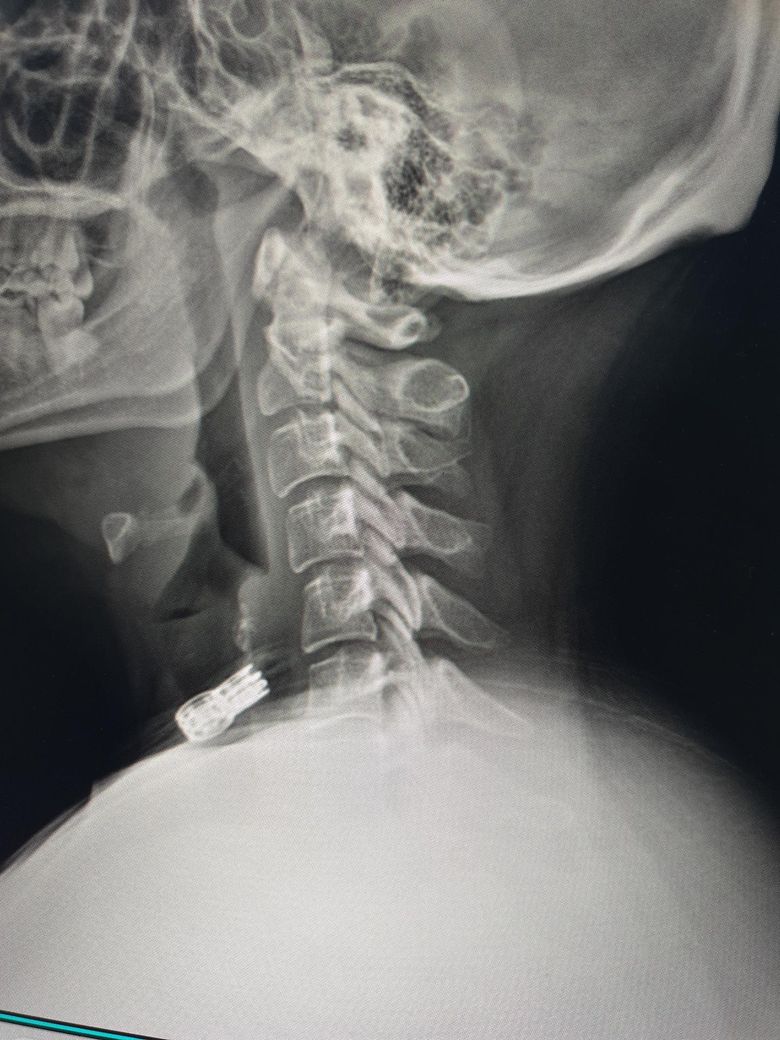

지금 현재 목 상때입니다 지금 오른쪽 목 신경이 시작하는 부분이 많이 아프고(후두동맥 부분) 신경이 뻣치는 느낌이 있어요 가만히 있어도 통증이 있습니다 지금 베개는 안맞는건지 불편해서 깨거나 신경시 뻣치는 느낌이 나서 깨요 가격대는 4만원까지 생각하고 있고 등이랑 어깨가 말려있어서 높이 않으면 숨이 막혀요 옆으로 누워서 자구요

• 2번 째 사진